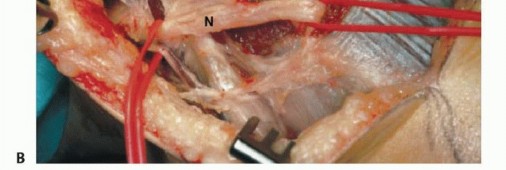

تُعد الشظية القريبة (الرأس والجزء العلوي من العظم) موقعًا رئيسيًا لالتصاق الرباط الجانبي الوحشي (LCL) ووتر العضلة ذات الرأسين الفخذية. هذه الروابط ضرورية لاستقرار مفصل الركبة الجانبي. الأهم من ذلك، أن العصب الشظوي المشترك يلتف حول قاعدة رأس الشظية ليدخل نفق العضلة الشظوية الطويلة، مما يجعله عرضة للإصابة أثناء جراحة الأورام في هذه المنطقة.

- الإجراء: يشمل إزالة الشظية القريبة، وغلاف عضلي رقيق من جميع الأبعاد، وموقع ارتباط الرباط الجانبي الوحشي (LCL). يتم الحفاظ على العصب الشظوي المشترك وفروعه الحركية، ويتم استئصال المفصل الظنبوبي الشظوي داخل المفصل.

- الحفاظ: يتم الحفاظ على العصب الشظوي والشريان الظنبوبي الأمامي عادةً.

- الإجراء: يشمل إزالة الشظية القريبة والمفصل الظنبوبي الشظوي، والحجرات العضلية الأمامية والجانبية، والعصب الشظوي، والشريان الظنبوبي الأمامي بشكل كامل. يتطلب هذا النوع ربط الشريان الظنبوبي الأمامي وقد يتطلب أيضًا التضحية بالشريان الشظوي.